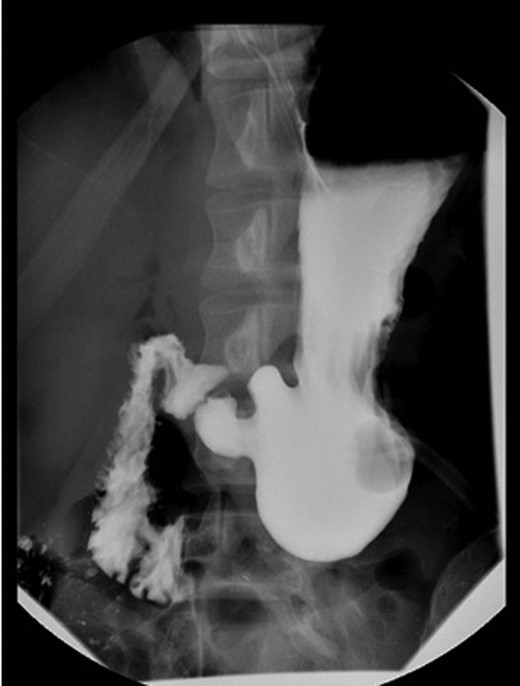

The laboratory results of the patient were creatinine 1.10 mg/dl (0.60–1.00), serum glucose 124 mg/dl (65–100), hemoglobin 16.9 µl (12.0–16.0) and total bilirubin 1.6 mg/dl (0.2–1.0). A gastroenterologist was consulted and an urgent EGD was done, showing negative insufflations of the stomach that were characteristic of a volvulus. The diagnosis of mesenteroaxial volvulus was confirmed by single contrast upper GI (UGI) imaging (Fig. 1).

The patient underwent a laparoscopic gastrostomy-tube gastropexy. A 10 mm laparoscope and three 5 mm ports were placed. There was no evidence of a hiatal hernia, diaphragmatic hernia or Meckel's diverticulum on visualization. The patient had healed well from his previous appendectomy. A crease on the stomach was visible where the volvulus had occurred. A 24-French gastrostomy tube was inserted percutaneously into the stomach and inflated. Using the gastrostomy tube, the stomach was approximated to the posterior aspect of the anterior abdominal wall. A point along the greater curve of the stomach, distal to the volvulus, was chosen to suture the stomach to the abdominal wall with permanent sutures. The patient tolerated the surgical procedure well (Fig. 2) and was discharged 4 days later.